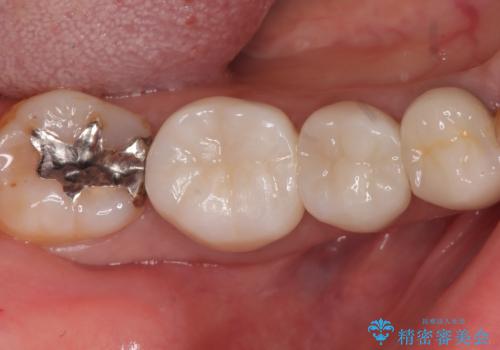

【セラミックインレー】笑うと銀の詰め物が目立つ

- 主訴:下の歯に詰まっている銀が笑うと見えて嫌だから白くしたい

右下7番目の歯に保険適用のメタルインレーが入っており、大きなう蝕などは認めなかったため概形は大きく変えずセラミックインレーへやり替えとなりました。